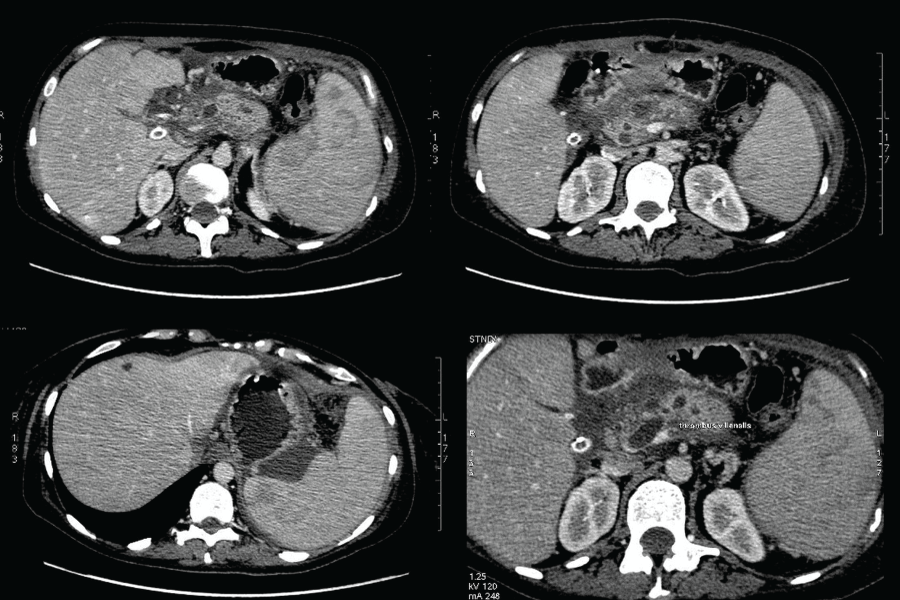

The examination of the papilla of Vater with a duodenoscope found no pathologic changes. Despite conservative therapy that achieved hemodynamic stabilization the patient was again with melena, with blood secretion from the contact drainage (600 ml) and persistent secretion from the transcystic drainage (500- 600 ml/24h). Endoscopic retrograde cholangiopancreatography (ERCP) was performed and revealed fresh bleeding from the ampulla of Vater. Selective cannulation and contrast of the pancreatic duct found a distal stenosis about 20 mm by length. At the level of the stenosis there was a cystic lesion, followed by a dilatation of the pancreatic duct in the body up to 15 mm with defects in the lumen/possible coagulum/, extravasation of the contrast from the duct to the body/tail pancreatic zone with contrasting of the left diaphragm cupola and the end of the contact drainage. A7Fr 13 cm pancreatic stent with side holes was placed to cover the lesion of the pancreatic duct in the tail. A distal stenosis of the choledochal duct was also detected due to a possible compression by the pseudocyst in the pancreatic head. Papilla sphincterotomy (PST) and placing of a 10 Fr 7 сm stent were performed (Figure 2 and Figure 3). The control CT2 days later proved the correct position of the stents, reduced size of the pseudocyst and significantly reduced size of the liquid collection (Figure 4). After the ERCP was done a complete stop of the secretion from the retroperitoneal drainage was achieved. Pancreatic and choledochal stent replacements were performed every three months in our patient and during a 2 years follow-up period no relapse of GI bleeding was observed.